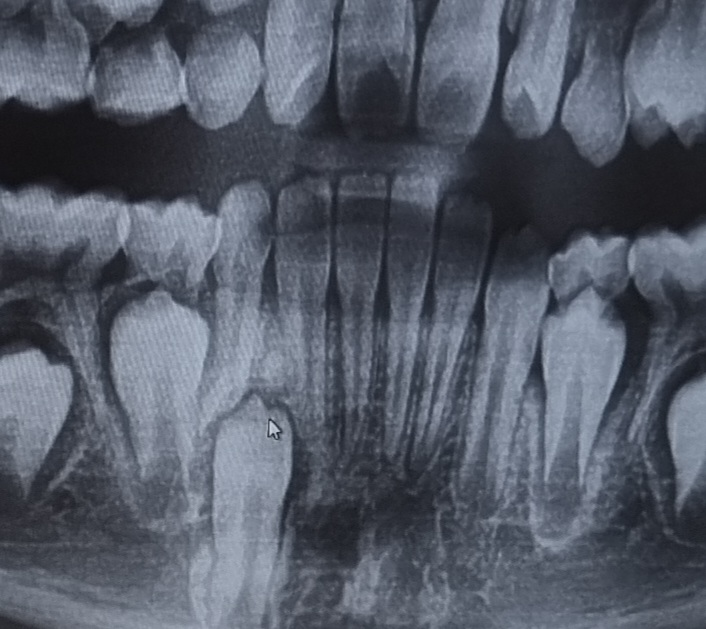

요 마우스위치의 뼈인지 치아인지때문에 나와야할 영구치가 못나오고있는것같다는 주치의 의견듣고왔네요.

• 1번 째 사진

말씀하신 부위가 뼈이거나 치아로 인하여 맹출이 지연되고 있음이 보입니다. 물론 정확한 것을 판단하기 위해서는 해당 부위에 ct를 촬영해보아야 할 것으로 보입니다. 뼈이거나 치아가 맞다면 대학병원 방문 후 해당 부위의 유치를 조기 발치하고 뼈나 치아를 제거한 다음에 영구치 맹출을 유도해야할 것으로 보여집니다.